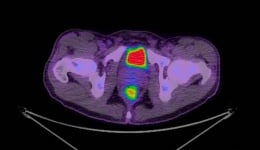

Smarter scans help blood cancer patients

A Peter Mac-led clinical trial has found combination PET/CT scans are better at investigating the causes of prolonged fever in blood cancer patients than conventional CT scans. The randomised